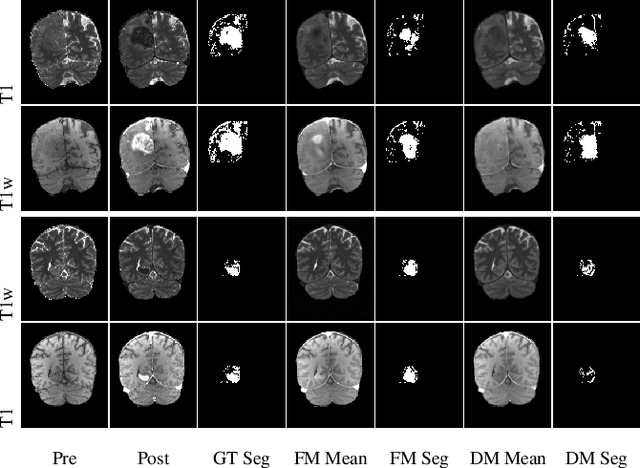

Abstract:Contrast enhancement by Gadolinium-based contrast agents (GBCAs) is a vital tool for tumor diagnosis in neuroradiology. Based on brain MRI scans of glioblastoma before and after Gadolinium administration, we address enhancement prediction by neural networks with two new contributions. Firstly, we study the potential of generative models, more precisely conditional diffusion and flow matching, for uncertainty quantification in virtual enhancement. Secondly, we examine the performance of T1 scans from quantitive MRI versus T1-weighted scans. In contrast to T1-weighted scans, these scans have the advantage of a physically meaningful and thereby comparable voxel range. To compare network prediction performance of these two modalities with incompatible gray-value scales, we propose to evaluate segmentations of contrast-enhanced regions of interest using Dice and Jaccard scores. Across models, we observe better segmentations with T1 scans than with T1-weighted scans.